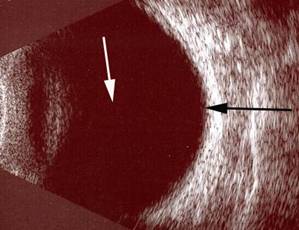

Resim 3: Göz içi yabancı cisim ve vitreus kanaması mevcut olan hastanın ultrasonografi görüntüsü. Altta göz içi yabancı cisime ait daha opak (beyaz) bir görüntü (siyah ok), normalde homojen siyah olması gereken göz sıvısının kanama sonucu yer yer opaklaştığını görmek mümkündür (beyaz ok).